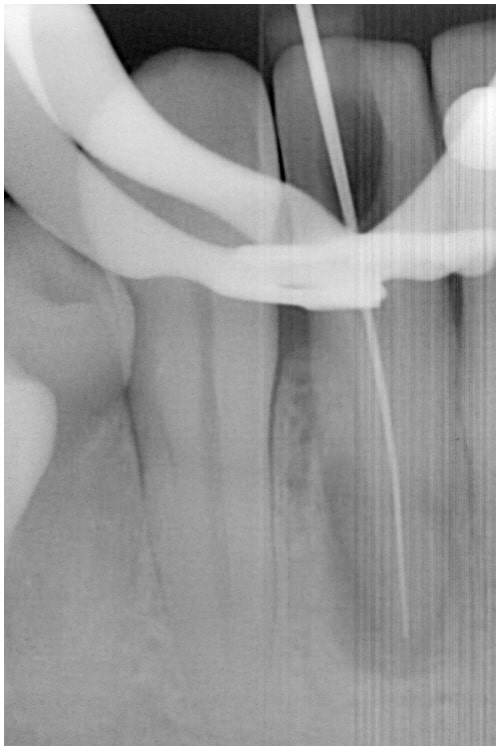

治療途中

症例4 非外科 病変あり 前歯 治療途中